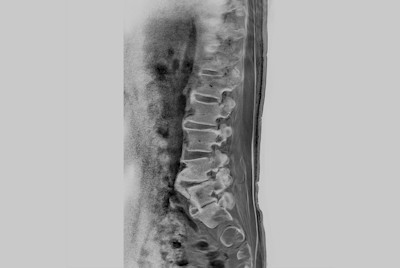

Lumbar Spine fracture with SmartSpeed Precise

Total Spine metastasis

Lumbar Spine in under 10 minutes total exam time

Total Spine on BlueSeal magnet

Pediatric Total Spine with spina bifida

Lumbar Spine with metal suppression

Lumbar Spine disc herniation

Lumbar Spine bulging disc (Compressed SENSE)

Lumbar Spine stenosis (Compressed SENSE)

Lumbar Spine with mDIXON XD

Total Spine with mDIXON XD TSE